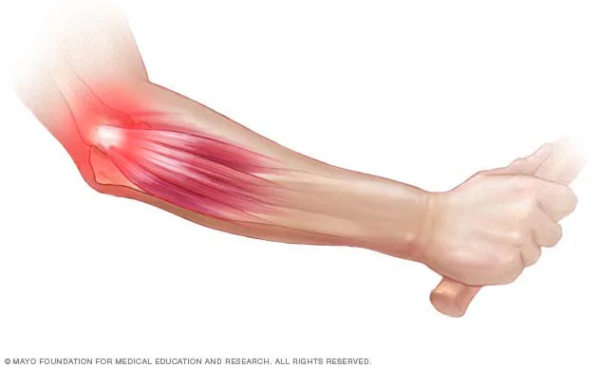

Codo de tenista en tenis, o epicondilitis lateral, es una tendinopatía de los tendones extensores del antebrazo que se insertan en la parte externa del codo. En tenis, se relaciona con gestos repetidos como el revés, sobre todo a una mano, y con impactos descentrados que obligan al antebrazo a “sujetar” vibraciones extra. El resultado es dolor y sensibilidad en la zona externa del codo al golpear, agarrar o levantar peso.

La zona dolorosa típica está en el lateral externo del codo, donde se insertan los tendones extensores de la muñeca y los dedos. Cada vez que sujetas la raqueta, ajustas el ángulo de la muñeca o estabilizas el impacto, esa musculatura trabaja. Si el gesto técnico no acompaña, el codo acaba haciendo de “amortiguador” de muchas fuerzas que podrían repartirse mejor.

En el revés a una mano, el brazo dominante tiene que generar potencia, controlar el ángulo de la cara de la raqueta y soportar las vibraciones del impacto. Cuando llegas tarde, golpeas muy atrás o tiras demasiado de la muñeca, la carga sobre el epicóndilo se dispara.